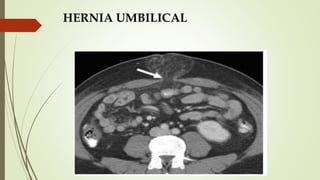

HERNIA UMBILICAL

 Protrusión del contenido abdominal (grasa epiploica ±

intestino) en o a través de la pared abdominal anterior

por el anillo umbilical.

 Congénita/Adquirida.

 Aumento de la presión intraabdominal: obesidad,

gestación múltiple, ascitis.

 DIAGNÓSTICOS DIFERENCIALES:

 Onfalocele: defecto congénito en la pared abdominal a

nivel del ombligo.

 Hernia ventral: epigástricas encima del ombligo,

hipogástricas debajo.

 Hernia de Spiegel: protruye en la línea semilunar y el

borde lateral del músculo recto.